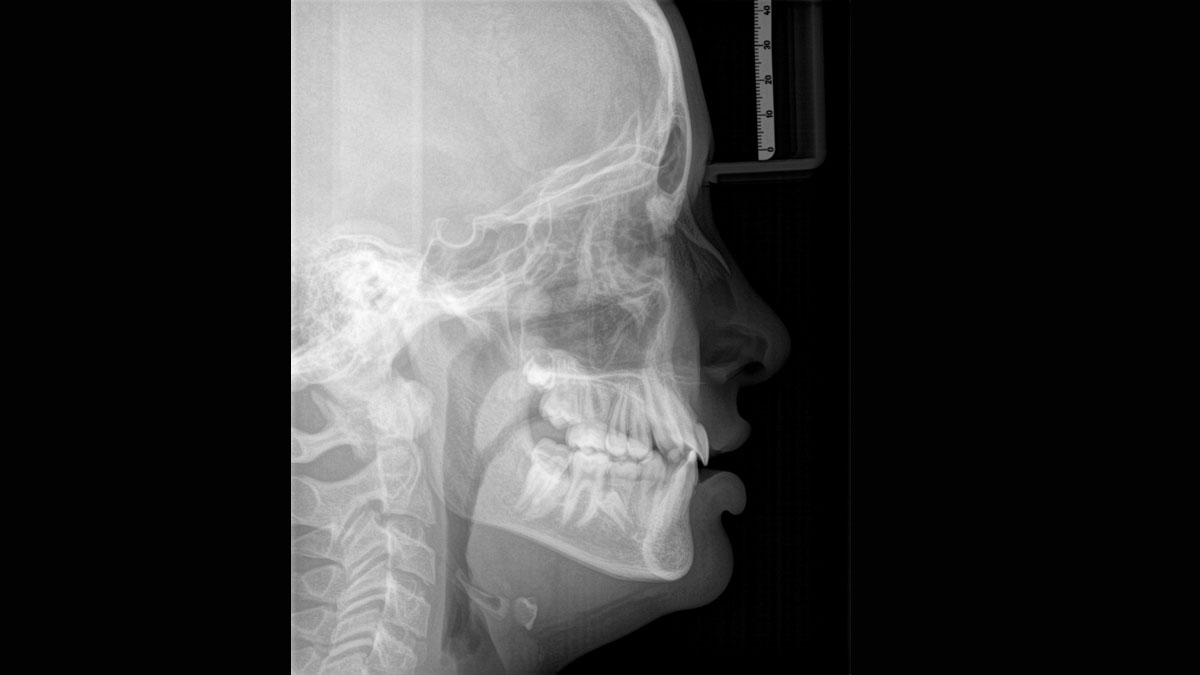

The high-quality 2D/3D X-ray device with a comprehensive range of services for every practice. Whether as a pure 2D device or including a 3D module – the Orthophos S is a reliable partner and optimized for everyday tasks. Its CsI Plus sensor with autofocus function ensures clear images, even in anatomically difficult cases. The automatic patient positioning together with the patented occlusal bite block enables an easy and timesaving patient positioning. For use in orthodontics, the Orthophos S is also available with an optional ceph arm. And because future-proofing is important to Dentsply Sirona, the cephalometric arm can be retrofitted at any time.

The ceph arm can be added on the right or left side of the unit and ordered at the time of purchase or retrofitted at any time